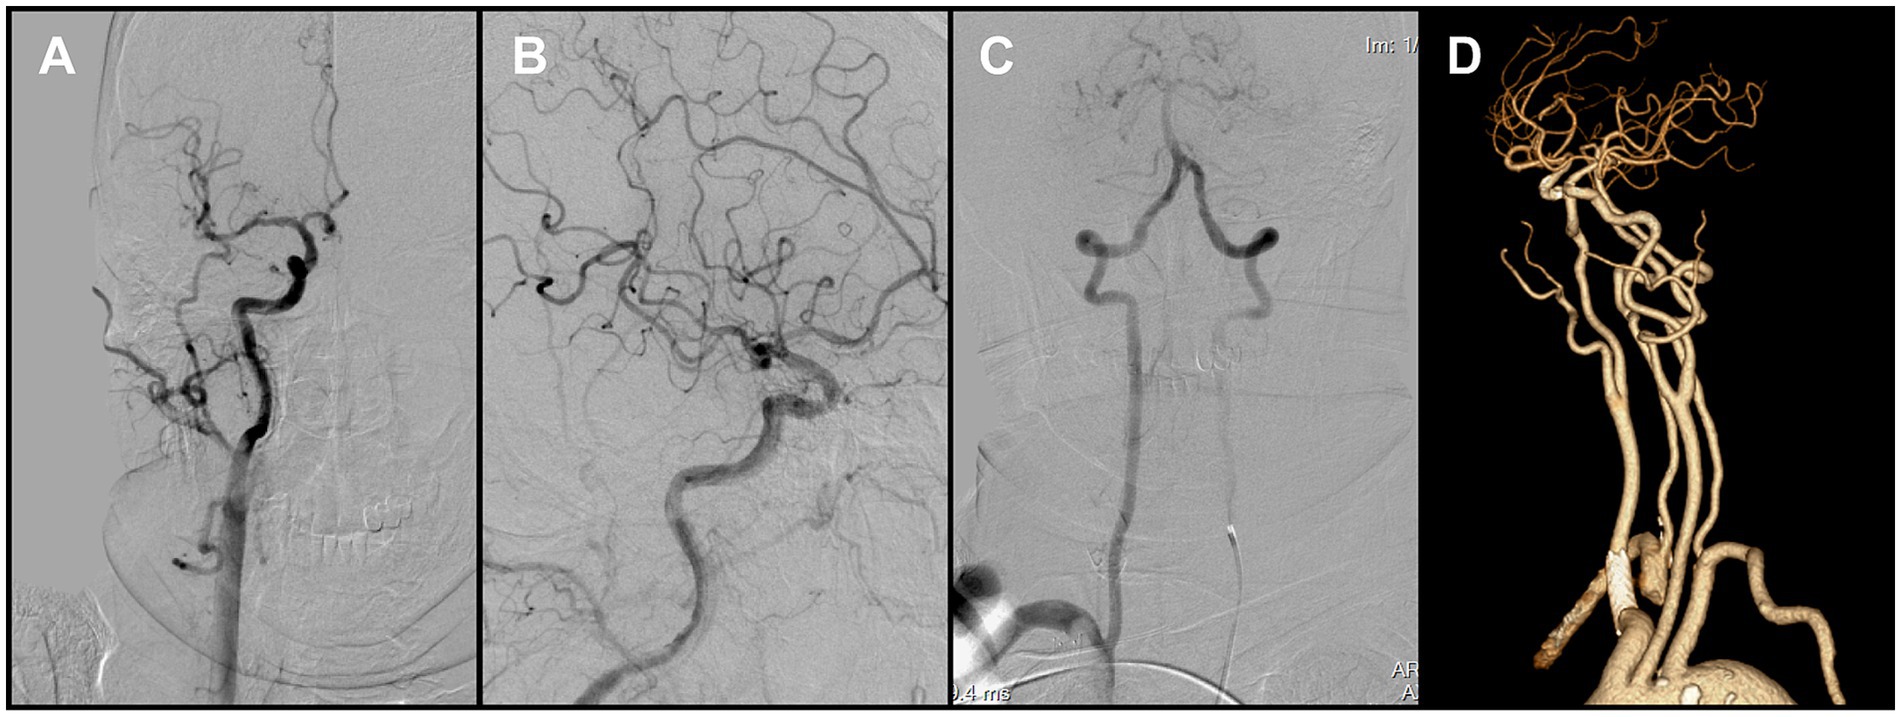

Because en bloc retrieval across the bifurcation carried high risk of embolic escape and recurrent cerebral embolism, an in situ stabilization strategy was selected. Under distal protection with a SpiderFX device, a self-expanding PROTÉGÉ 9 × 40 mm stent (Medtronic, USA) was deployed in the CCA to pin and compress the thrombus against the vessel wall without predilation. Post-deployment angiography confirmed the ICA remained widely patent, with no residual stenosis (Figure 3D). The previously noted intracranial emboli had resolved spontaneously, and the final reperfusion grade improved to mTICI 2C (Figures 4A,B). Before completion of the procedure, angiography of the left vertebral artery demonstrated patent posterior circulation vessels with retrograde opacification of the right vertebral artery, indicating preserved collateral flow and minimal risk of thrombus migration from the right subclavian artery into the intracranial circulation (Figure 4C).

Figure 4. (A,B) Final angiography prior to procedural completion demonstrated reperfusion of the right carotid system (mTICI grade 2C). (C) Left vertebral angiography showed retrograde flow in the right vertebral artery. (D) Follow-up CTA at 1 month demonstrated persistent occlusion of the right subclavian artery.

Follow-up CTA at 1 month confirmed persistent occlusion of the right subclavian artery (Figure 4D). Clinically, the patient remained asymptomatic, with no upper-limb ischemic symptoms and no significant inter-arm blood pressure difference. Conservative management was therefore adopted, with surveillance imaging as planned. Referral for vascular surgical or endovascular revascularization was reserved for the development of arm ischemia, disabling symptoms, or a hemodynamically significant inter-arm pressure discrepancy. The patient showed marked neurological improvement and was discharged on the above regimen. At the 3-month clinical follow-up, the modified Rankin Scale (mRS) score was 0, indicating complete functional recovery.